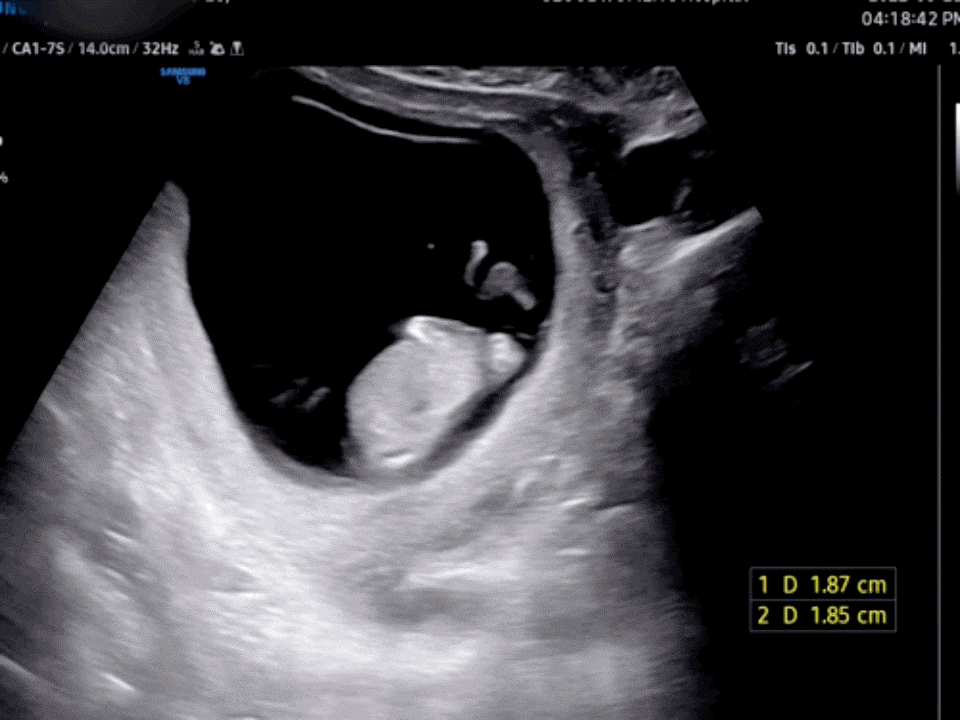

초음파를 보다가 나를 놀라게 한 이 사진! 설마 이거 고추예요?

의사 선생님께서 11주에는 음경인지 음핵인지 모른다고 하셨다. 여자 아이든 남자 아이든 다 뛰쳐나오고 16주가 되면 여자 아이는 들어오고 남자 아이는 더 튀어나오니까 그때 정확하게 성별을 알려준다고 했다.